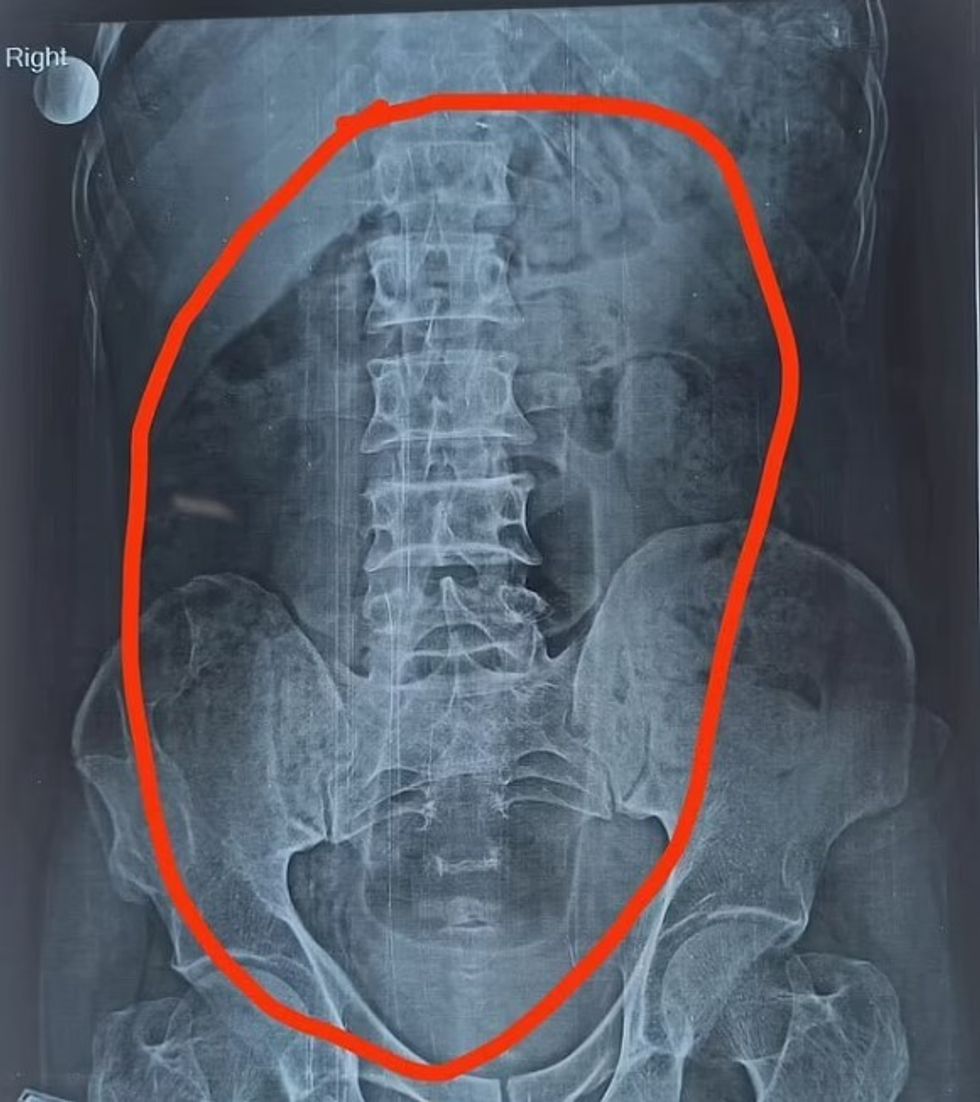

Ai kishte shkuar në spital me dhimbje të mëdha barku, e pas kryerjes së rëntgenografisë, është konstatuar se bëhet fjalë për shishe deodoranti që i kishte mbetur në bark.